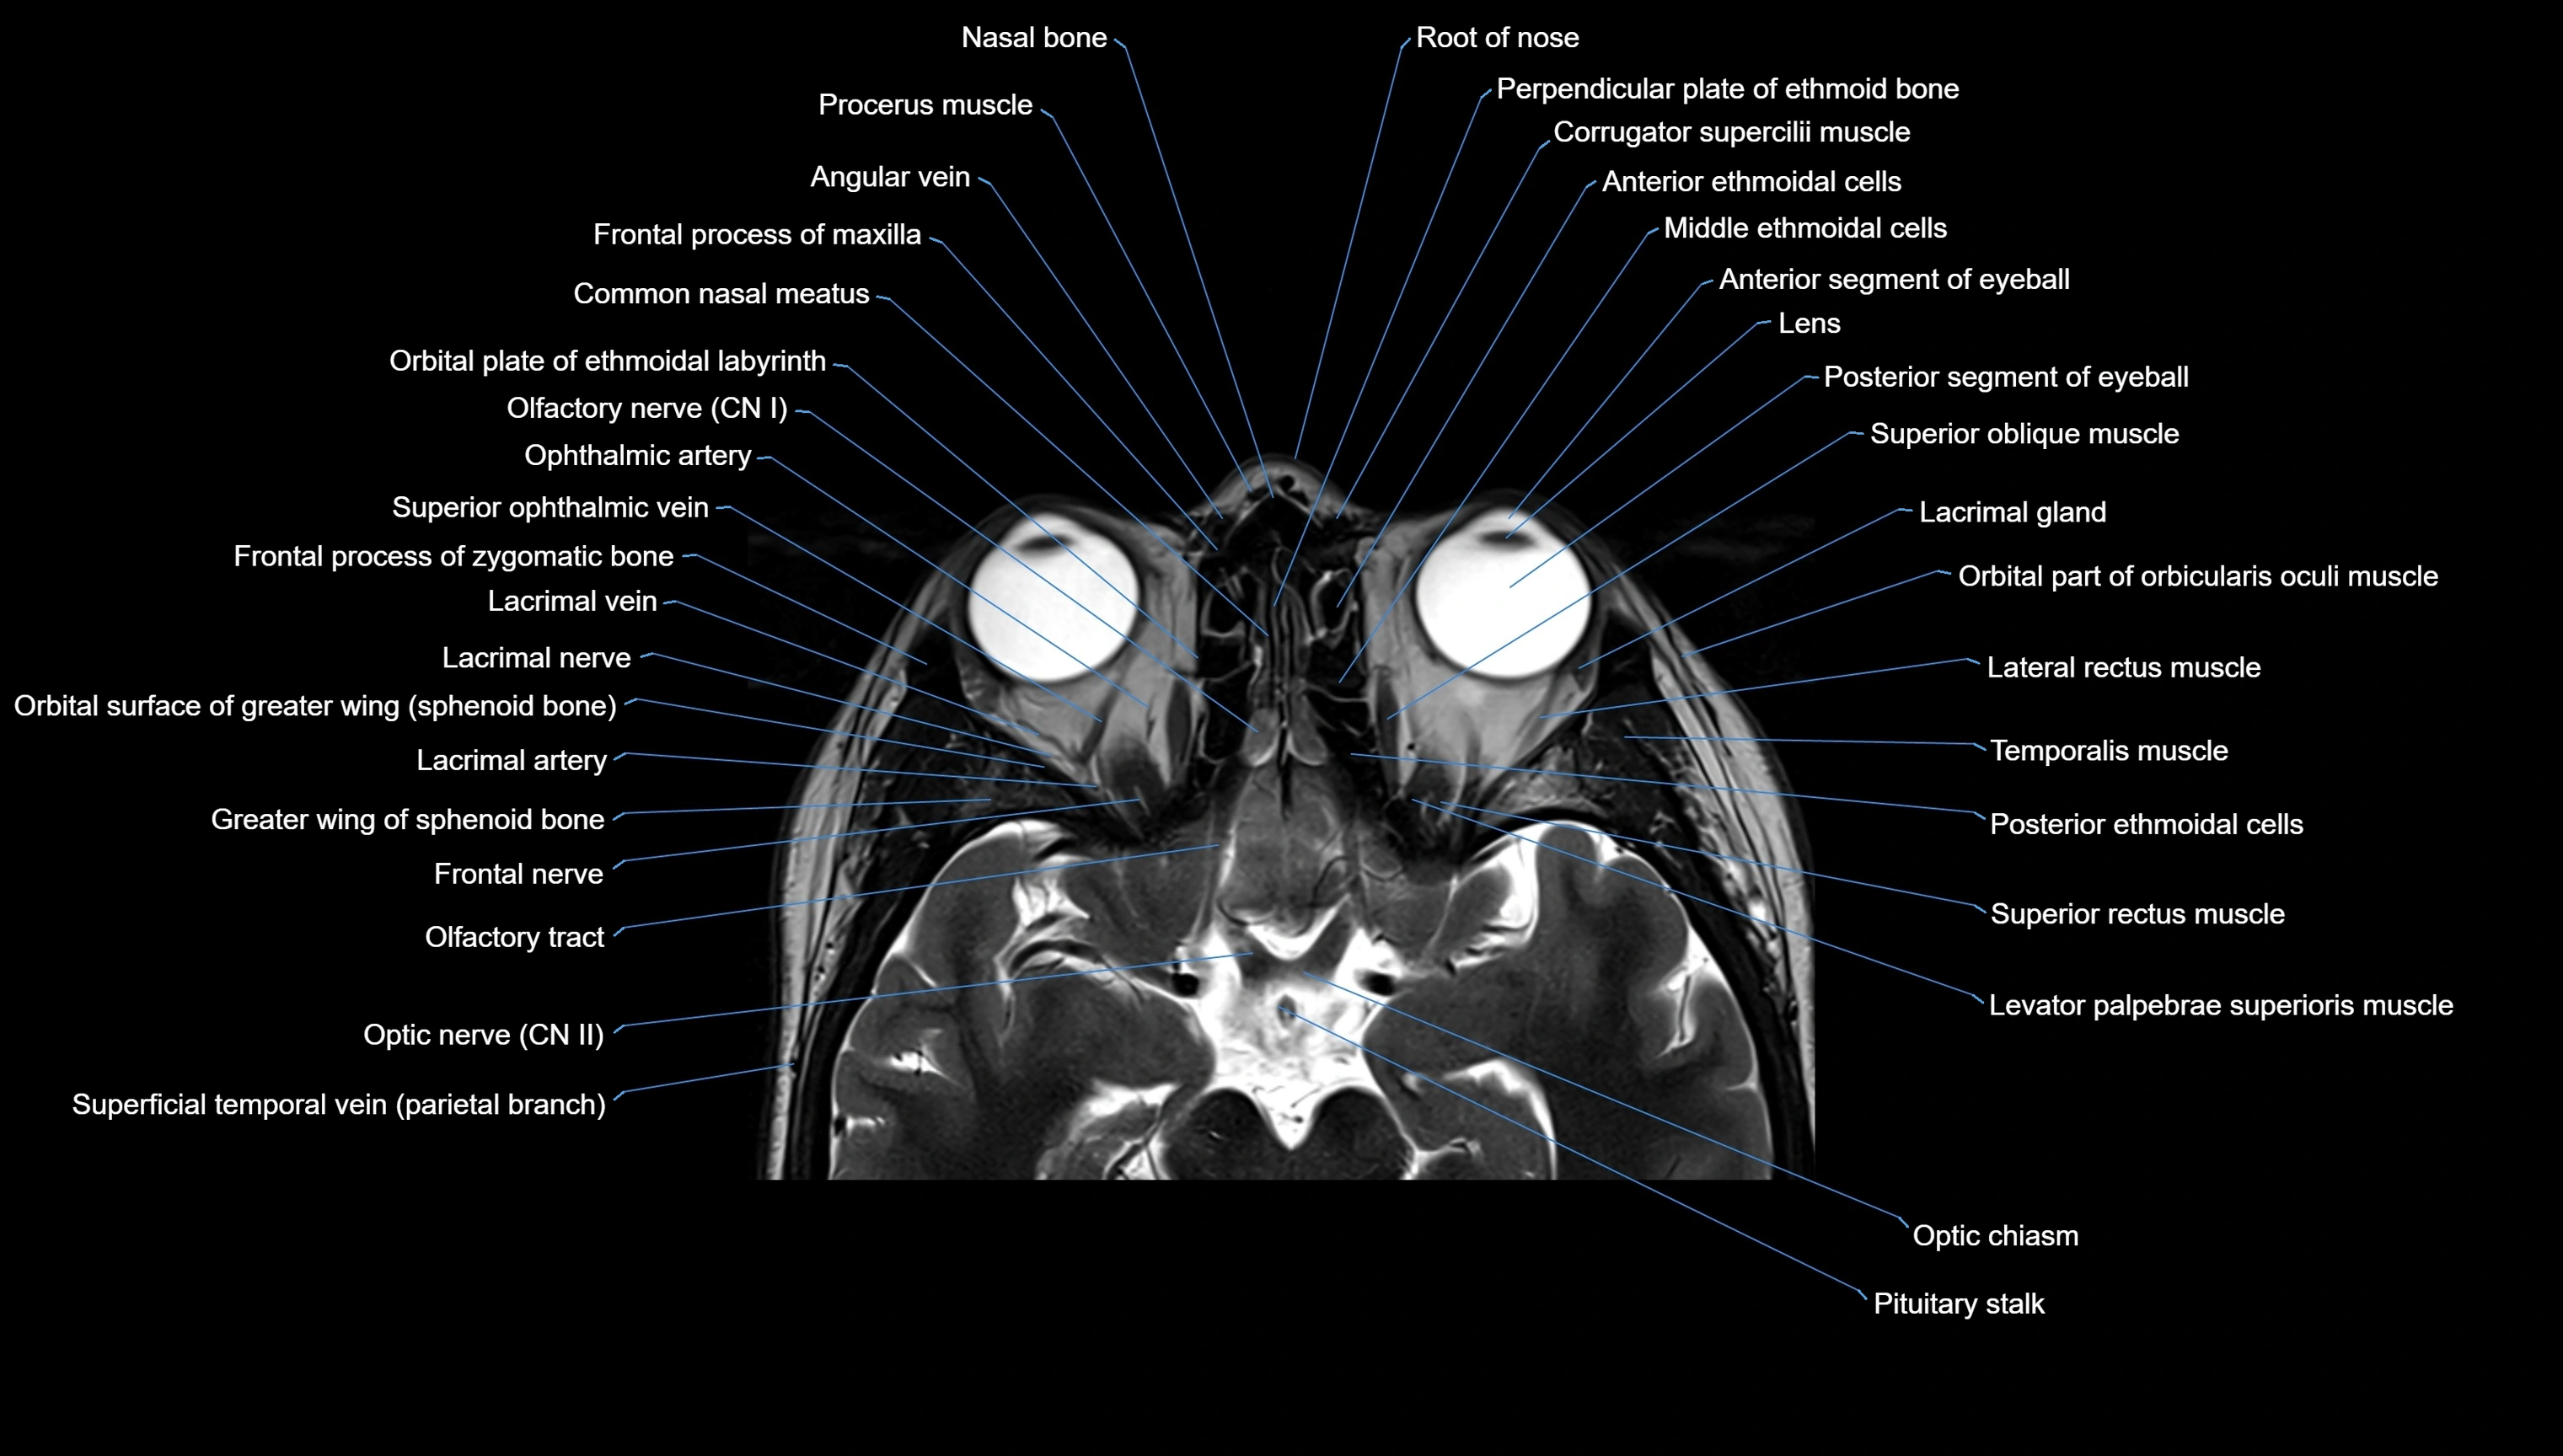

- Olfactory Nerve (Cranial Nerve I)

- Olfactory tract

- Optic Nerve (Cranial Nerve II)

- Optic chiasm

- Lacrimal gland

- Lacrimal nerve

- Lacrimal artery

- Lacrimal vein

- Lateral rectus muscle

- Levator palpebrae superioris muscle

- Superior oblique muscle

- Superior rectus muscle